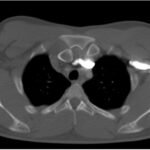

Posterior sternoclavicular dislocations are very rare and pose immediate threat to mediastinal structures should a patient sustain this type of injury. This case report discusses the presentation and diagnosis of a young male who presented with isolated right arm swelling after blunt trauma one day prior while participating in a bull riding rodeo event. He was diagnosed with posterior right sternoclavicular joint dislocation with compression of the left brachiocephalic vein that was seen on computed tomography (CT) angiogram study. Patient was transferred to a tertiary care center for a higher level of care and definitive reduction management. Any history of blunt shoulder trauma or direct sternoclavicular trauma with symptoms to suggest compression of mediastinal structures should make one suspicious for posterior sternoclavicular dislocation. Evaluation is best made by computed tomography (CT) scan. Reduction should be performed by an orthopedic surgeon in the operating room with cardiothoracic surgery available for any vascular compromise that may occur.